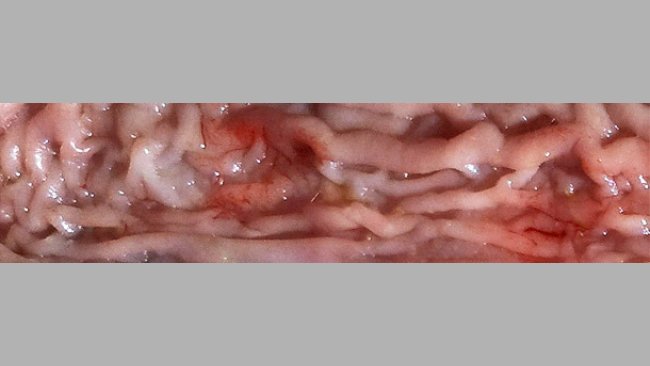

In questo 2° articolo Antonio Vela, Francisco José Pallarés e David Espigares rispondono a domande sulla diagnosi, il monitoraggio e l'eradicazione della pleuropolmonite causata da Actinobacillus pleuropneumoniae (App)...